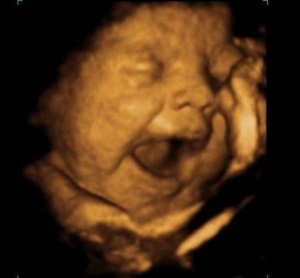

Bebekler ana karnında 'ağlama provası' yapıyor